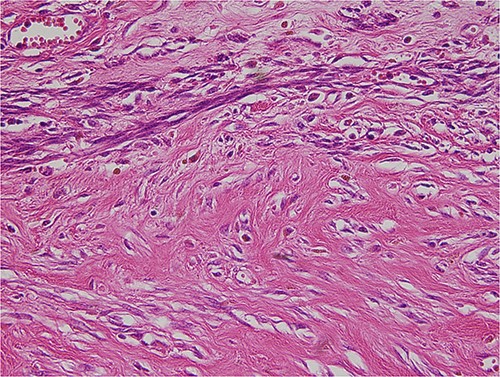

The tumor was wrapped in a grayish-white capsule in a lobulated pattern, accompanied by bleeding; necrosis was not apparent. Yellow dot-like cellular components were observed. The findings for the spindle cell neoplasm (46.5 × 25.0 × 8.0 cm) were a smooth-muscle tumor of uncertain malignant potential (stump), with necrosis absent, a mitotic count <4/10 HPF, and moderate-to-severe and focal nuclear atypia (Fig. 3). Based on these results, the diagnosis revealed that the tumor originated from smooth muscle cells and was classified as a spindle cell tumor. Immunohistological analysis showed negative results for CD34, c-kit, PAN-CK, EMA, and S-100 and positive results for Desmin and SMA. The Ki-67 index was 5% (Fig. 4).

The tumor was composed of spindle cells with moderate to severe, focal nuclear atypia.